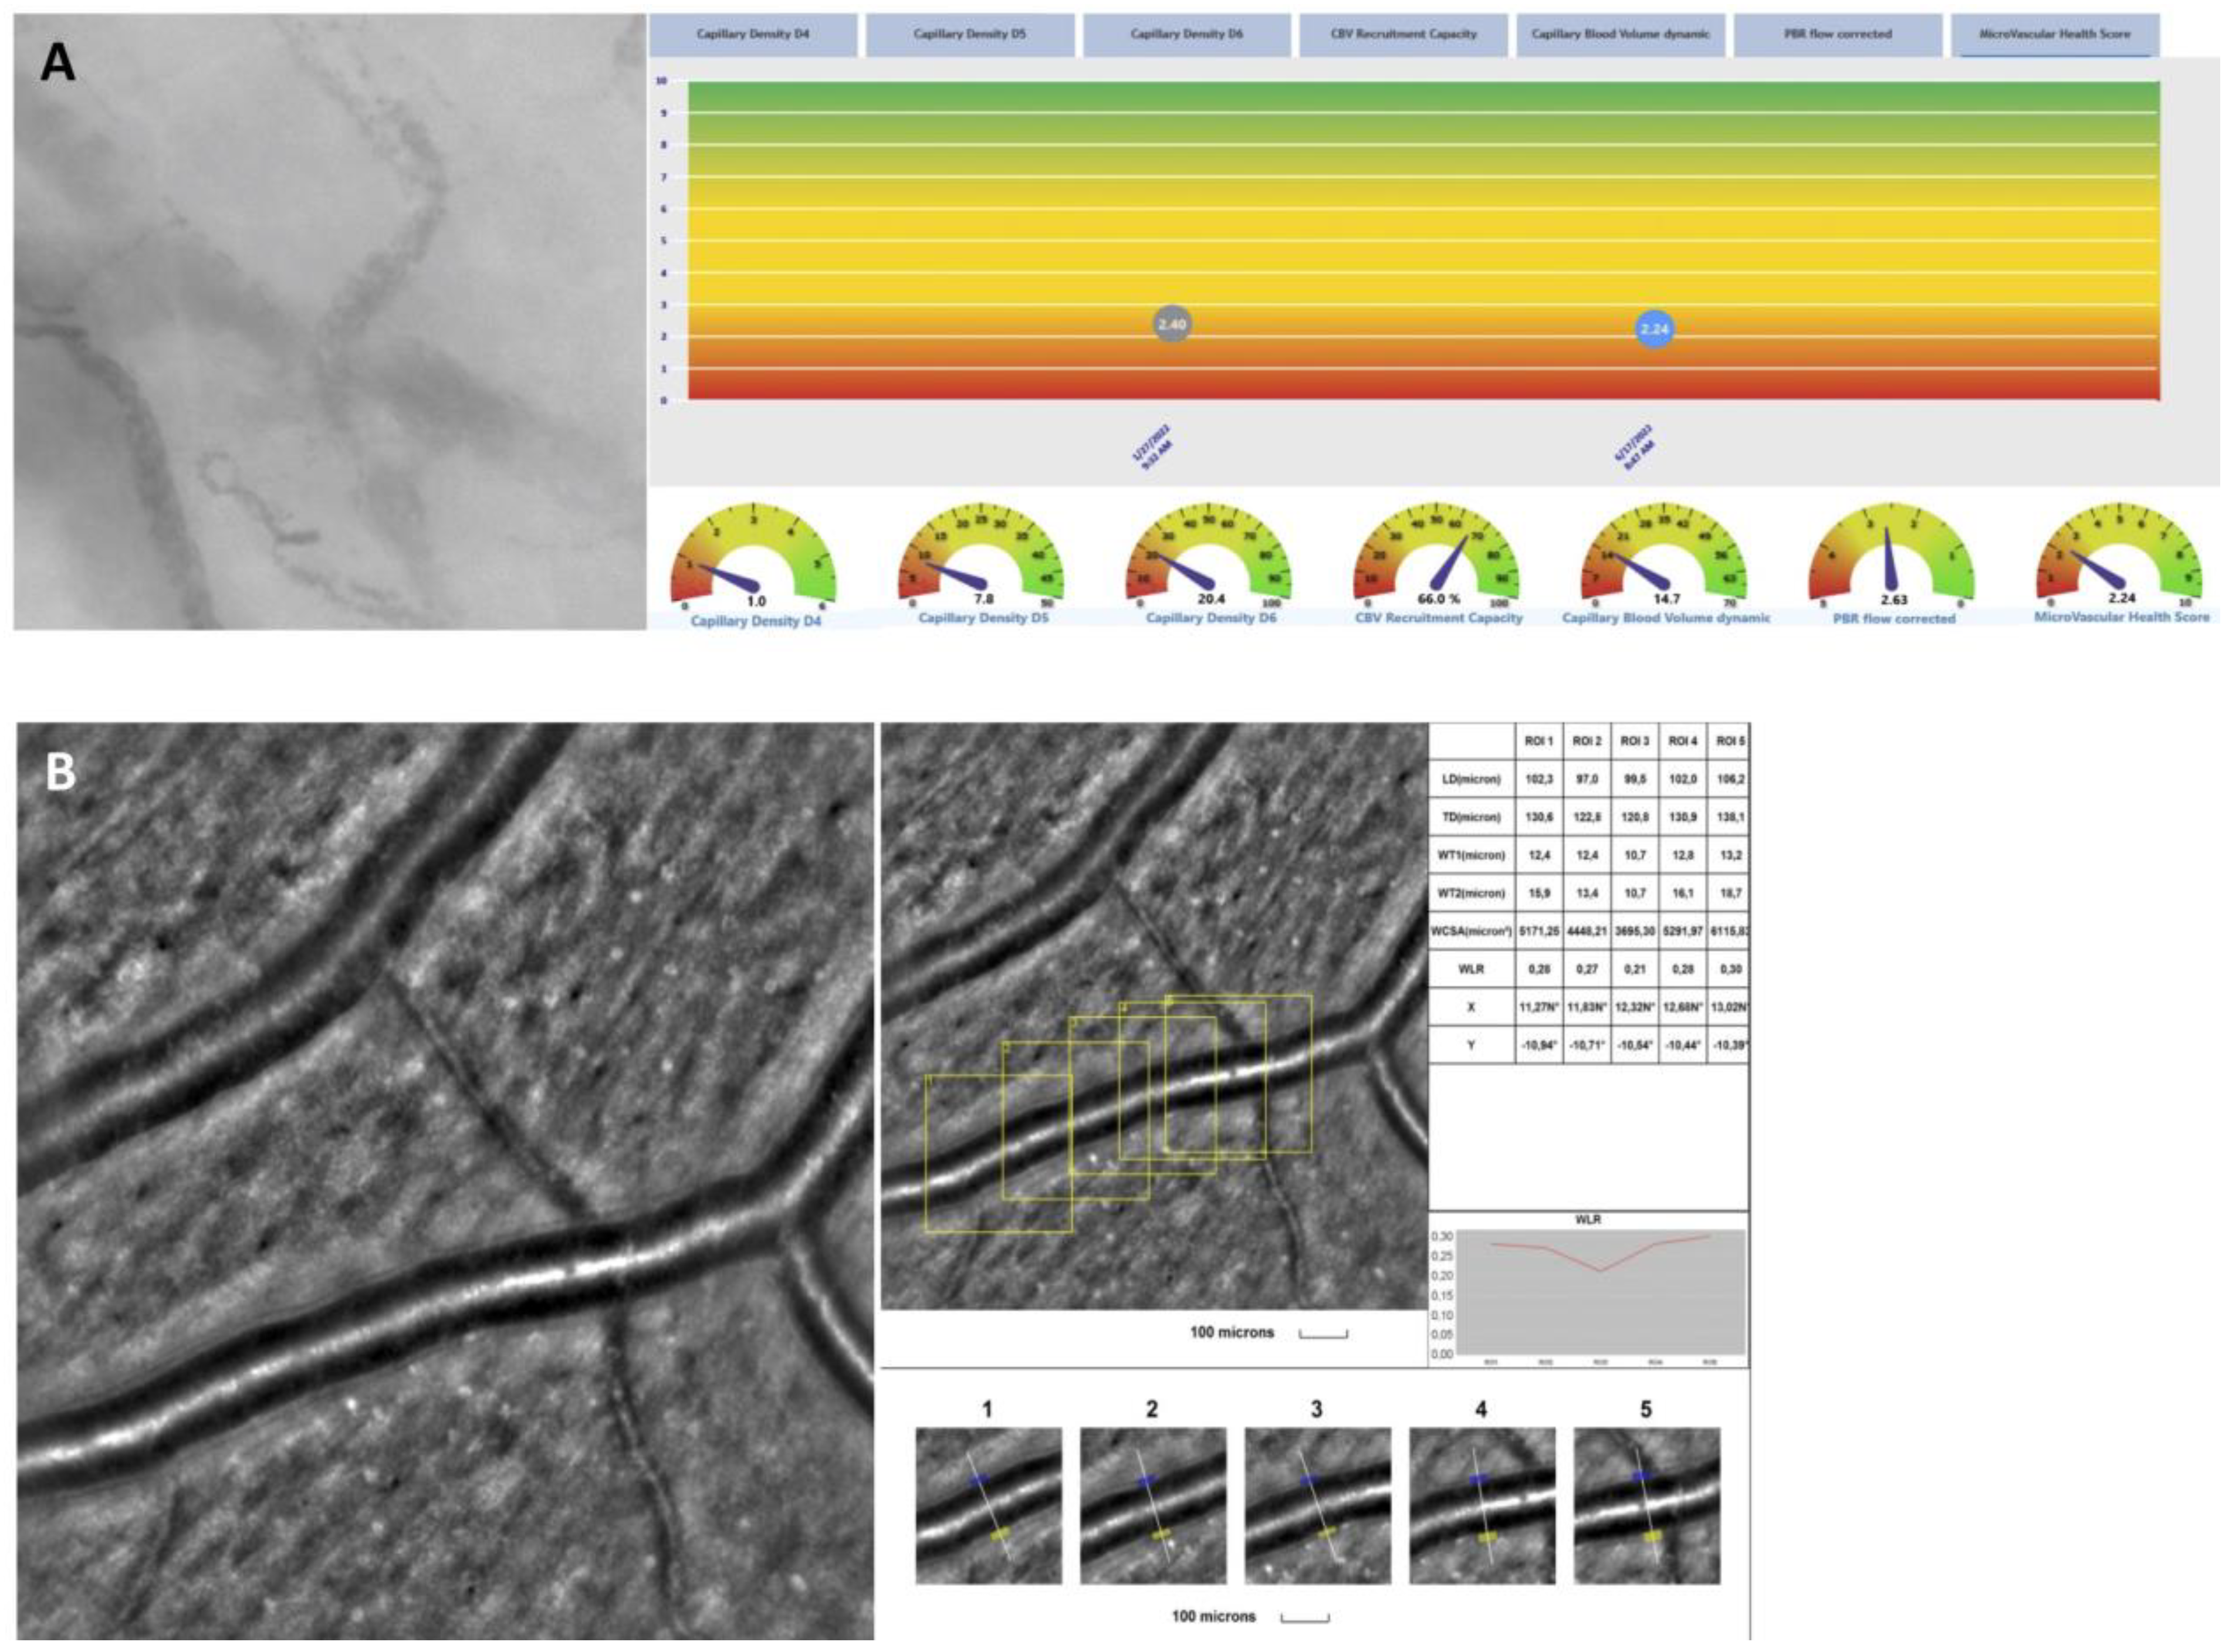

2.5. rtx1 Examination Protocol and Parameter Evaluation

2.6. In Vivo Assessment of the Microcirculation and Glycocalyx Dimensions

3.2. Adaptive Optics

| Adaptive Optic (88 Eyes) | |

|---|---|

| WLR, μm (mean ± SD) | 0.3 ± 0.0 |

| WCSA, μm2 (mean ± SD) | 3931.4 ± 907.7 |

| WT, μm (mean ± SD) | 12.1 ± 1.9 |

| GlycoCheck (44 patients) | |

| Number of exams per patient (mean ± SD) | 14.6 ± 8.7 |

| PBR, μm (mean ± SD) | 2.2 ± 0.2 |

| Flow total density D4–D25, ×10−2 mm/mm2 (mean ± SD) | 166.8 ± 63.0 |

| Capillary density D4–D6, ×10−2 mm/mm2 (mean ± SD) | 23.9 ± 12.2 |

| CBVdynamic (mean ± SD) | 13.2 ± 8.4 |

| MVHS (mean ± SD) | 2.4 ± 1.6 |